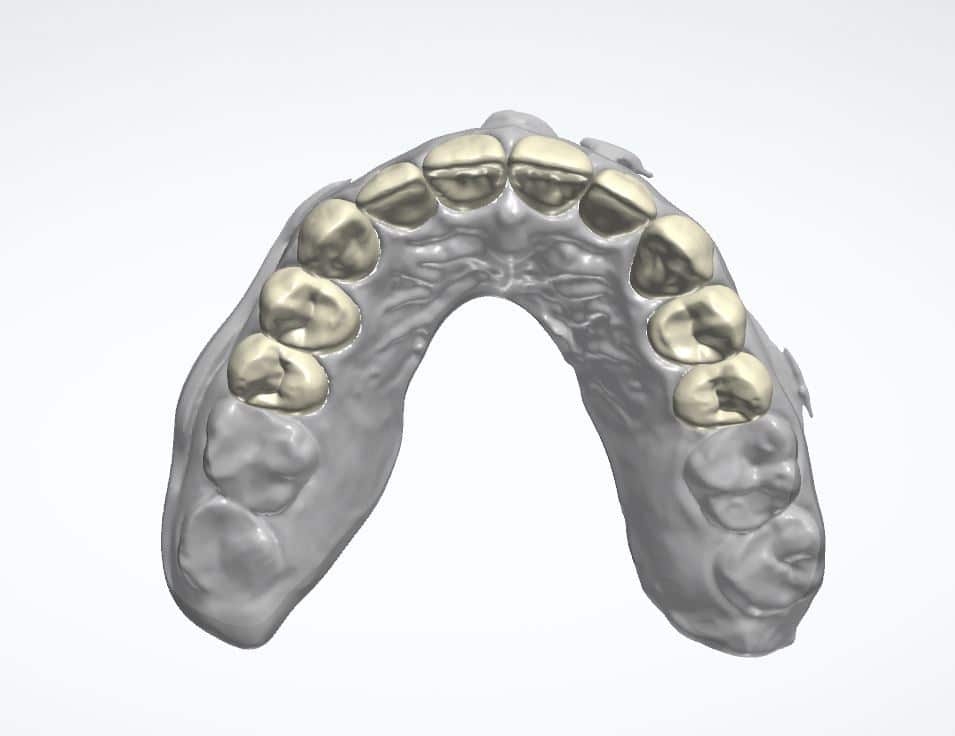

Anschließend wurden die Zähne 15 bis 25 präpariert und die Präparationen mit einem Intraoralscanner erfasst. Auf der Grundlage der STL-Daten der digitalen Abformung wurden im Dentallabor des Autors die Kronen aus PMMA mit der De-sign-Software 3Shape geplant (Abb. 11 bis 13). Dabei erstellte die Software aus dem 2-D-animierten Bild einen 3-D-Out-put (Abb. 11). Diese STL-Datei wurde dann händisch in die Konstruktionssoft-ware eingesetzt und wie zuvor mit der

Patientin verabredet sowie dem Smile-cloud-Vorschlag entsprechend positio-niert. Dieser Vorgang – die Umsetzung des 2-D-Smile-Design-Vorlage in eine 3-D-Konstruktion, erfolgt also nicht au-tomatisiert. Mit einem CAD/CAM-Frässys-tem mit fünf simultan arbeitenden Achsen wurden die Provisorien passgenau gefräst (Abb. 14 und 15).